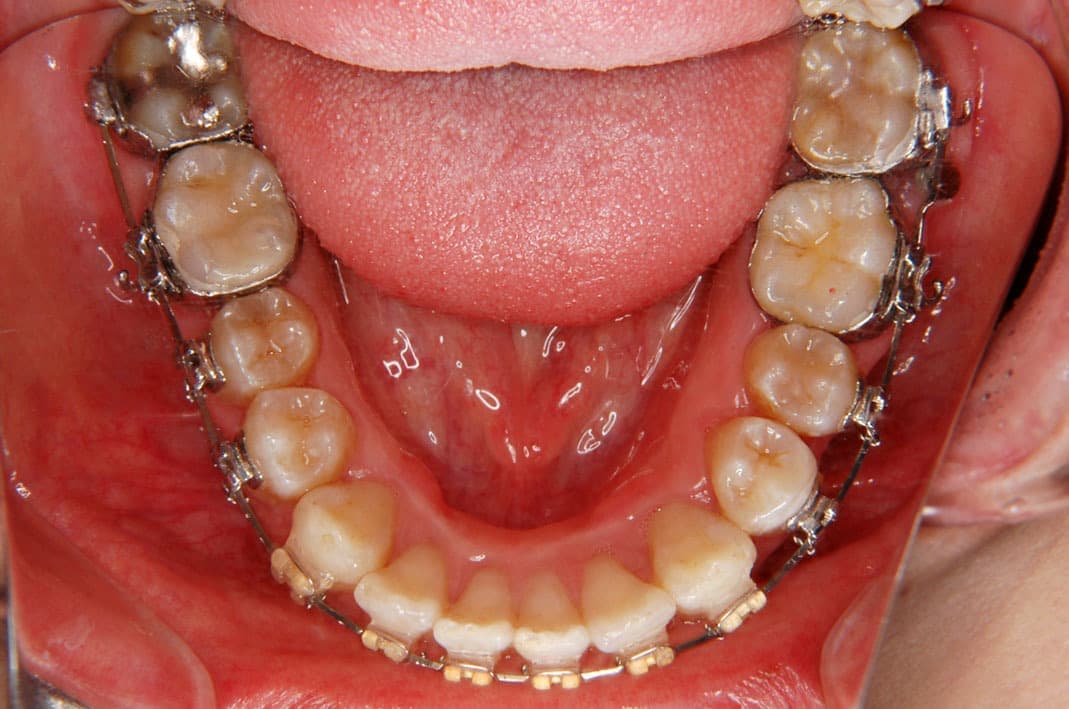

歯科矯正用アンカースクリューの使用例

例1)

➡︎